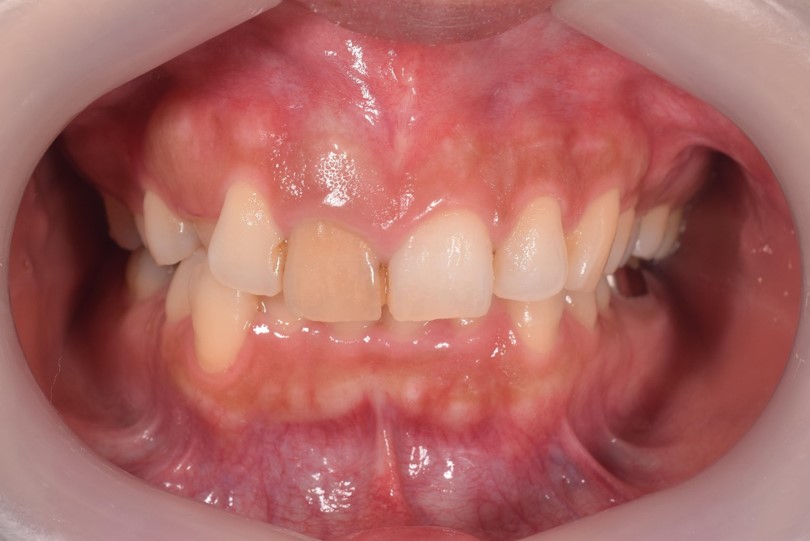

歯の色調がどうしても出せない場合、褪せてしまった歯を透明感のある歯に被せ物でよみがえらせる処置があります。